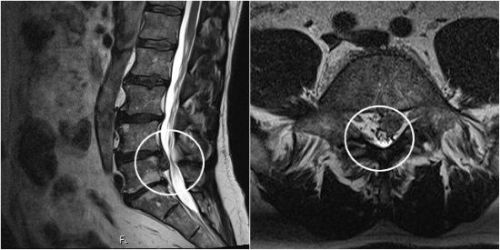

Наиболее частым последствием остеопороза является межпозвонковая грыжа. Она представляет собой смещение части межпозвонкового диска, который подвергся деформации. Чаще всего заболевание возникает в поясничном отделе позвоночника. Многие пациенты интересуются, можно ли увидеть грыжу позвоночника на рентгене. Поскольку межпозвонковый диск – это фиброзно-хрящевое образование, которое хорошо пропускает рентгеновские лучи и выглядит на снимке как участок просветления, грыжа на рентгенограммах не визуализируется.

О наличии данной патологии можно судить из текущего расстояния между позвонками: если они сместились на 4 мм и более, врач делает предположение об образовании грыжи.

Одна из разновидностей заболевания – грыжа Шморля – прорыв в тело позвонка хрящевой ткани из межпозвонкового диска. Грыжа Шморля на рентгене (снимки представлены ниже) проявляется вогнутостью замыкательных пластинок внутрь тела позвонка. Вокруг очага патологии расположены белые участки затемнения (остеосклероз – патологическое повышение плотности костной ткани), в зоне губчатого вещества – серо-черные участки просветления (остеопороз – снижение плотности костной ткани). Говоря проще, грыжи Шморля выступают из диска вверх и вниз в тела соседних позвонков, и протекают бессимптомно, в отличие от классических протрузий и грыж, когда диск деформирован в горизонтальной плоскости, с возможной компрессией сосудисто-нервных пучков.